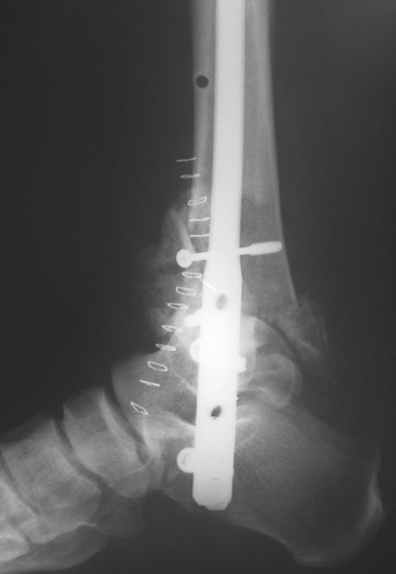

Michael Berenstein 24 Сентябрь 2004, 11:36

Nail arthrodesis for failed pilon fracture is good solution.

My example

Michael Berenstein